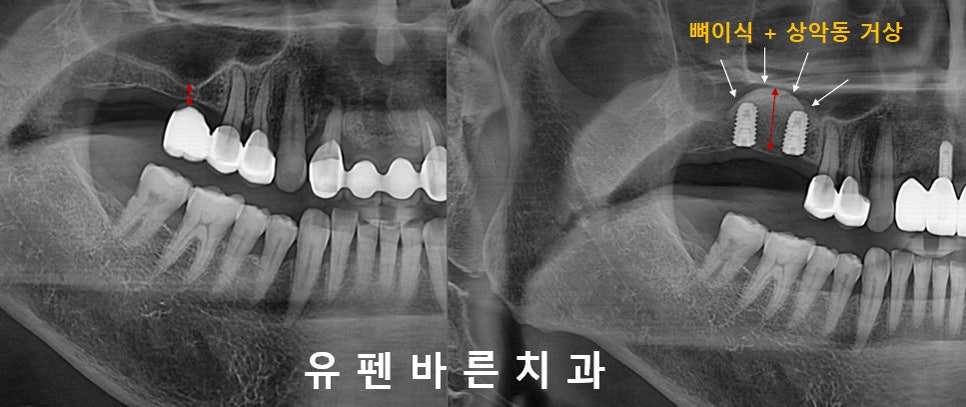

(첫번째 케이스)

Teeth No. #2,3 Sinus Augmentation

왼쪽 위사진을 보시면

인공뿌리(임플란트)를 식립하기에는

빨간 화살표 처럼

뼈의 높이가 많이 짧아 보입니다.

이런 경우

그냥

임플란트만 식립하게 되면

임플란트 길이의 80%가 단단한 뼈안에

고정되지 않고

상악동의 허공에

뜨게 됩니다.

헉!!!

그렇게 되면

임플란트가 뼈에 제대로 고정되지 못하고

흔들리며

임플란트 실패의 결과로

이어지게 됩니다.

따라서!

오른쪽 위사진의

빨간색 화살표 만큼의

상악동 거상(들어올림)과

인공뼈이식을 통해

충분한 뼈높이를 만든 후

임플란트를 식립해야

안전하고 이상적인 임플란트 수술을

마칠 수 있습니다 :)

마무리 된

상악동 거상과 뼈이식이

반구형 모양(Dome-Shape)으로

아주 예쁘게 잘 올라간 모양을

보실수 있습니다.